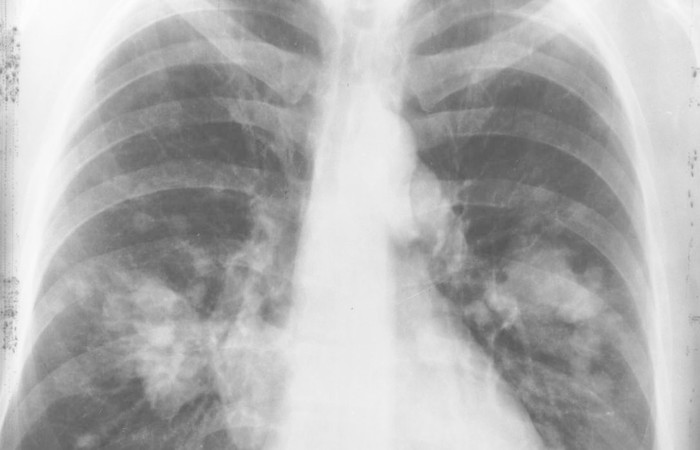

A Sociedade Brasileira de Patologia (SBP) está reforçando a importância do diagnóstico com precisão máxima para pacientes com qualquer tipo de câncer. No caso do adenocarcinoma, o câncer de pulmão que acomete a apresentadora de TV Ana Maria Braga, nota da entidade reforça indicação de que seja feita análise molecular do tumor, ”pois dependendo das alterações genéticas encontradas, há alternativas específicas de tratamento, as chamadas terapias-alvo”.

O patologista Felipe D´Almeida Costa do Departamento de Anatomia Patológica do A.C.Camargo Cancer Center e membro da SBP acrescenta que a pesquisa de perfil molecular “consegue identificar qual o melhor tipo de tratamento para cada paciente”, mas é indicada “para os pacientes com doença avançada”. Para o adenocarcinoma em fase inicial, “a indicação é cirurgia e radioterapia”, explica.

O adenocarcinoma é um dos tipos de câncer no pulmão, carcinoma de pequenas células, que ataca a camada de células que reveste o órgão, e é considerado de desenvolvimento mais célere. “Quando o paciente tem um carcinoma de pequenas células são urgências oncológicas. Precisa tratar o quanto antes porque é um tumor muito agressivo”, alerta o especialista.

De acordo com D´Almeida Costa, a doença pode comprimir os vasos sanguíneos da região central do tórax e causar síndrome por congestão vascular e resultar inchaço no rosto por causa da compressão dos vasos sanguíneos. O paciente pode sofrer com dificuldade respiratória, acumular líquido na pleura (membrana que cobre o pulmão) e até sentir dor na coluna.